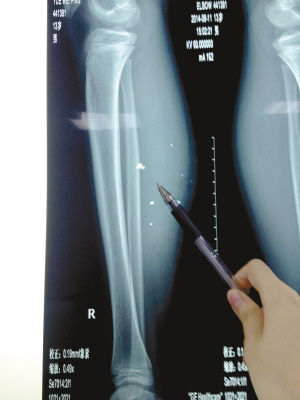

X光片顯示:手機電池內(nèi)的物質被炸進了小平的右小腿里

8月10日凌晨,小平轉院至重慶醫(yī)科大學附屬兒童醫(yī)院。小平的主治醫(yī)生骨科二病房周悅航醫(yī)生介紹,入院時小平右小腿腫脹,經(jīng)檢查,發(fā)現(xiàn)有爆炸傷伴異物殘留。傷口較深,約1.5厘米~2厘米,手機爆炸后進入患兒小腿的異物約有10處。周悅航說,由于進入皮膚的異物較多,已深入肌肉,且比較分散,最深的一塊貼近骨頭,可能需要多次手術。

另外,醫(yī)生擔心手機爆炸后金屬物進入患兒體內(nèi)可能會對患兒肌肉造成損傷,所以需盡快手術。據(jù)悉,8月14日上午,小平將接受小腿爆炸傷清創(chuàng)與異物取出術。